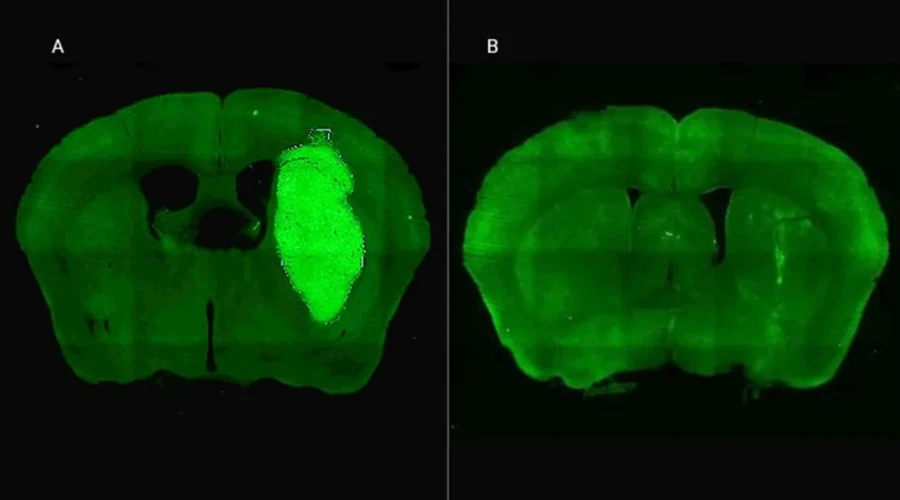

Candolfi y colegas utilizaron una terapia génica experimental basada en una molécula muy pequeña o péptido llamado P60, desarrollado por Juan José Lasarte en la Universidad de Navarra, en España, que atraviesa la membrana celular e inhibe la proteína Foxp3. “Cuando en experimentos de laboratorio bloqueamos Foxp3 utilizando P60, la respuesta de las células de glioblastoma a la radioterapia y a una variedad de drogas quimioterapéuticas mejoró notablemente”, destacó la investigadora del CONICET.

Además, P60 tuvo efectos antitumorales directos, reduciendo la viabilidad y la migración de las células de glioblastoma e inhibiendo la proliferación de células endoteliales que son clave para la progresión del tumor. Para evaluar estos efectos, los autores del estudio utilizaron una variedad de modelos celulares murinos (de roedor) y humanos. “En particular, los cultivos derivados de biopsias de pacientes con glioblastoma desarrollados por nuestro colaborador Guillermo Videla Richardson, del Instituto FLENI, son muy útiles para representar la heterogeneidad de estos tumores”, indicó Candolfi.